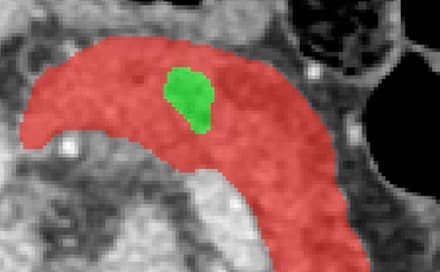

AI/ML, Backend

Multi-task deep learning pipeline for pancreatic cancer detection using nnUNetv2 and 300+ 3D CT scans with 82% accuracy.